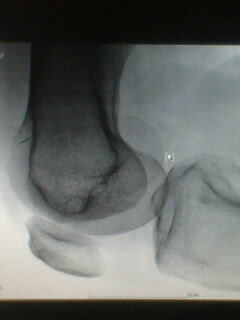

标题: X5658:膝关节改变?!

中年男性,外伤,疼痛!

股骨下段骨软骨瘤。撕脱性骨折

支持考虑骨软骨瘤,髁上突在肱骨内髁上方.本例股骨外髁关节面似有异常,但是可以是与髌骨重叠构成,必要时加照正位(稍内斜一点把髌骨让开)

宽基底与股骨干相连,背离关节面,支持考虑股骨下段外生骨疣

第二楼的回答是全面和正确的!

髌骨向外下移位,股骨下段骨软骨瘤。